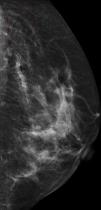

We present the case of a 52-year-old woman with a family history of breast cancer (mother) who came to the hospital for her annual mammography screening. Microcalcifications with a linear distribution following the skin folds were observed, predominantly in the upper outer quadrants of the breasts and in both axillary regions (Fig. 1).

It is therefore not uncommon to observe images with the density of calcium on plain x-rays or mammography in these patients; these images may have a linear distribution when they are produced by calcification of the elastic fibers in blood vessel walls. There may also be microcalcifications in the breasts and axillas due to calcification of the elastic fibers of the dermis,3 and it has even been suggested that these microcalcifications in the breast could be the result of calcification of the muscle fascia and of the interlobar septa of the gland.5

According to the study by Bercovitch et al.,5 breast microcalcifications may be detected in more than half of women with PXE. In the majority of cases these calcifications are isolated, although they have been reported to form groups in some patients,6 creating calcium-containing masses that would explain the presence of palpable nodules in both axillas, as occurred in our patient. The combination of breast microcalcifications and vascular calcifications is highly characteristic in these patients, and although it is not rare to detect either of these in the normal population, their combined presence should make us look in detail at the skin for the possible presence of changes suggestive of PXE. It has been reported that calcifications affecting vascular structures that contain elastic tissue can be observed on plain radiographs in up to a third of patients5 and calcification of the coronary arteries can give rise to symptoms that simulate those of arteriosclerosis.

In summary, although any calcification observed on mammography should be an alarm signal, it is important to know the frequency of association of mammographic microcalcifications with PXE and to take this into account in the differential diagnosis of breast cancer.7,8